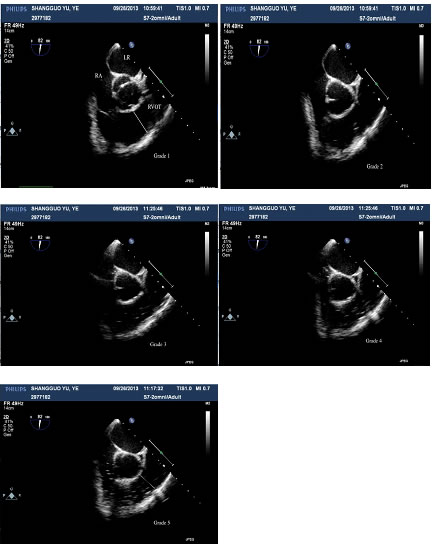

After the induction of anesthesia, a transesophageal echocardiography (TEE) probe was inserted via an esophagotomy, and the existence of a patent foramen ovale (PFO) was checked before the surgery. Patients were infused with 1 liter of Lactated Ringer’s solution before the operation. During the operation, special attention was paid to the right atrium (RA), right ventricle (RV) and right ventricular outflow tract (RVOT). TEE images were videotaped throughout the surgery. An independent cardiac anesthesiologist categorized GEs into five grades according to Schmandra’s classification system [9]: Grade 1, no bubbles in the RA, RV or RVOT; Grade 2, a single gas bubble in the RA, RV or RVOT; Grade 3, gas bubbles filling less than half the diameter of the RA, RV or RVOT; Grade 4, gas bubbles filling more than half the diameter of the RA, RV or RVOT; Grade 5, gas bubbles completely filling the diameter of the RA, RV or RVOT. Severe GE encompassed grades 4 and 5.

GEs occurred in 100% of the patients. As shown in Figure 1, five-grade embolism was detected by TEE during LH. The distributions of GE grades were similar in the two groups (Table 2). The frequencies of severe GEs (stage 4-5) were 54.2% and 76.0% in the P and S groups, respectively, but this difference was not statistically significant. A total of 20.8% of patients (n=5) in the S group and 16% of patients (n=4) in the P group experienced a severe GE of stage 5.

Figure 1: Five-grade embolism detected with TEE in one patient. RA: right atrium, LA: left atrium, RVOT: right ventricular outflow tract.